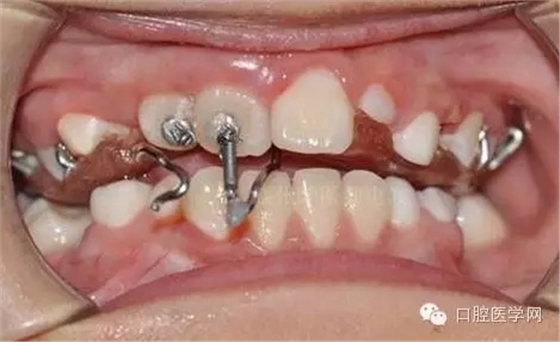

用時(shí)9周完成埋伏牙牽引。

孩子自信的微笑,是我們最大的幸福。